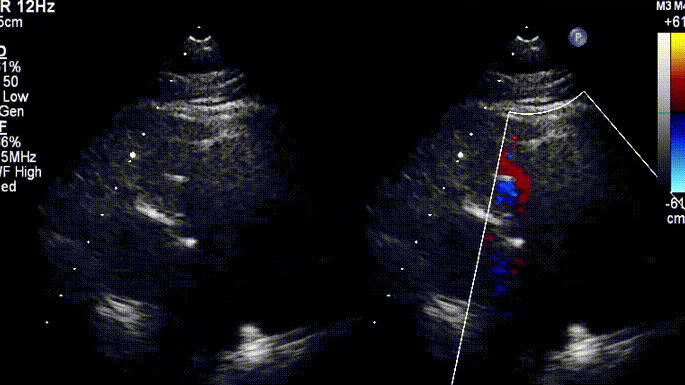

男性,45岁,法洛氏四联症术后35年,肺气肿病史,3年前行左肺肺结节切除术,患者6年前因体力下降,当地查出肺动脉瓣反流,未给予治疗。近2年来,活动耐量明显下降,步行数十米即感气喘,无法运动,体重增加后,活动耐量更差,入院前,患者自述“走几步路就觉气喘”。心超提示患者肺动脉瓣环内径约2.83cm,主肺动脉内经增宽,约4.61cm,频谱多普勒测及前向最大流速134cm/s,峰值压差7mmHg,舒张期探及大量反向血流信号(4+),瞬时量约17-21ml,三尖瓣轻度关闭不全,右房右室增大。

术前超声影像